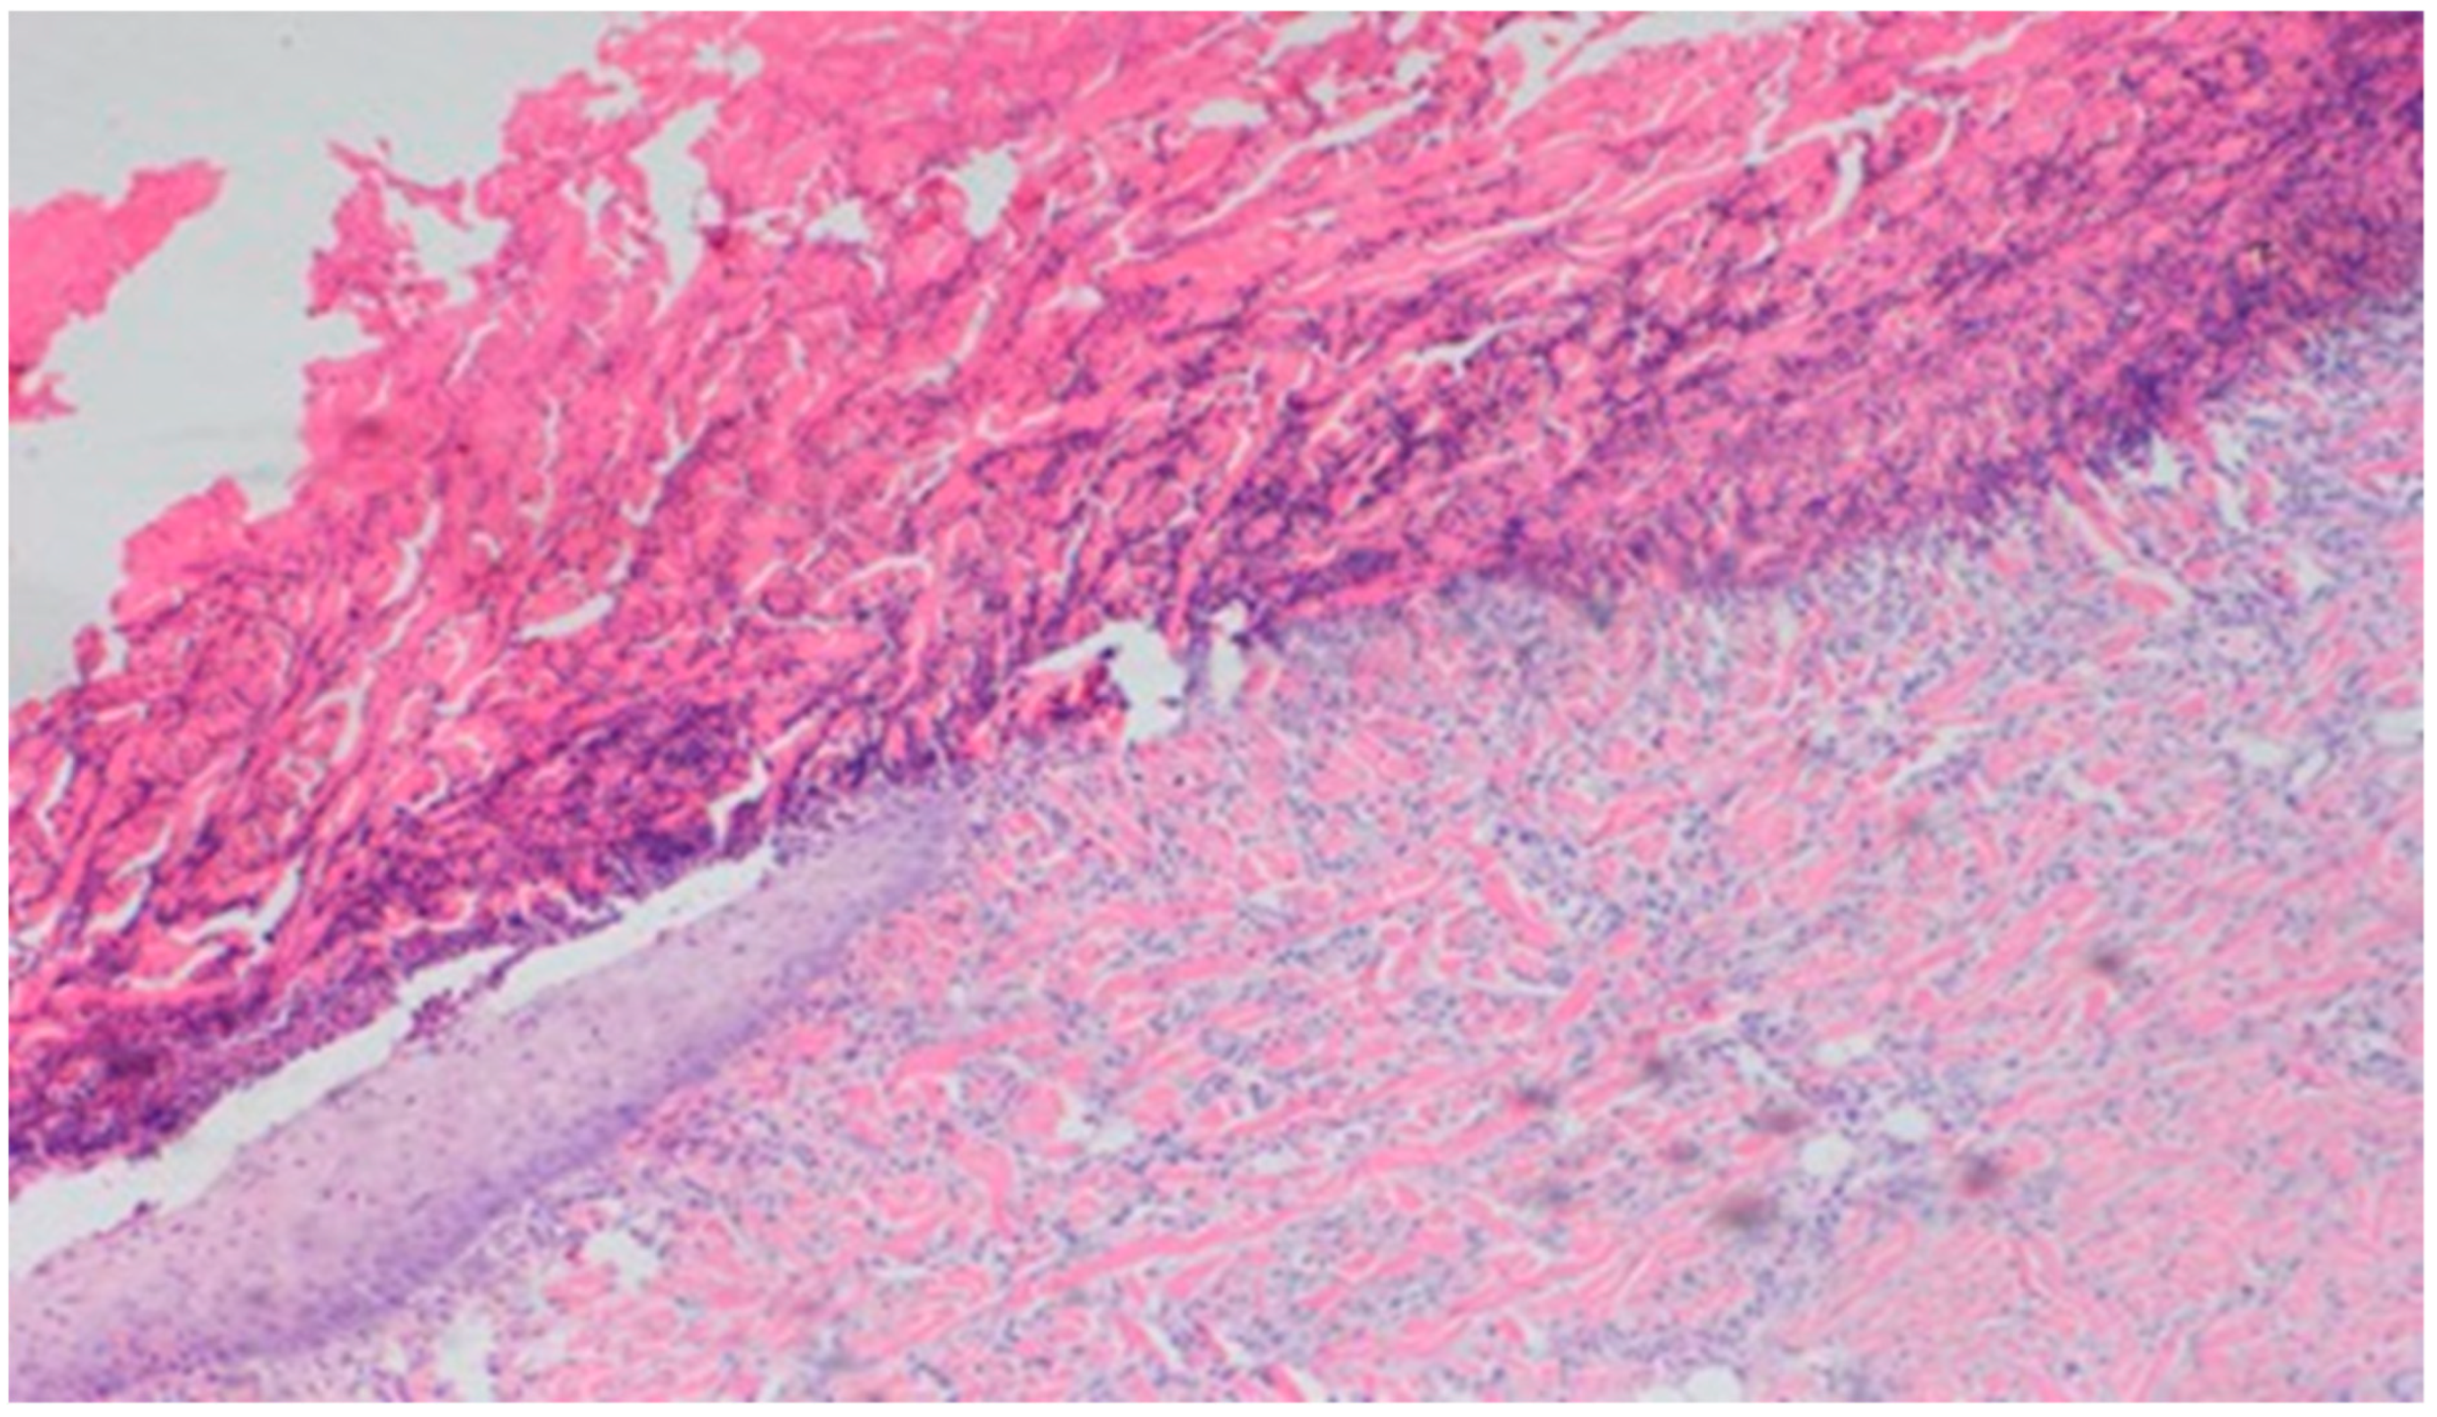

On day 10, all wounds in the control and experimental groups were characterized by a moderate inflammatory infiltration, with a predominance of granulocytes, reaching the dermis. In the experimental group D1, inflammation was at the same level as on the 5th control day. The experimental group D2 and the control group K, treated successively with the 1% nanosilver ointment and sulfathiazole, showed a greater intensity of inflammation in relation to the 5th control day. In group D3, treated with a mixture of 1% propolis and 1% nanosilver, a regression of the inflammatory infiltration, from large to medium, and depth, from adipose tissue to the dermis, was observed. In the experimental group D1, treated with the 1% propolis ointment and control K, treated with sulfathiazole, on day 10, a slight epidermization appeared. On day 10, additionally, all the wounds from the experimental and control groups showed slight superficial necrosis and were characterized by a moderate neovascularization. The histopathological findings from day 10 are presented in Table 9 and Figure 15, Figure 16 and Figure 17.

Figure 15. Granulocytic inflammatory infiltration, medium density.

Figure 16. Slight superficial necrosis. Moderately intense granulocytic inflammatory infiltration in the dermis (40×, H-E), in the wound treated with the 1% nanosilver ointment, on day 10.

Figure 17. Focal epidermization under superficial necrosis (100×, H-E) in the wound treated with the 1% propolis ointment on day 10.